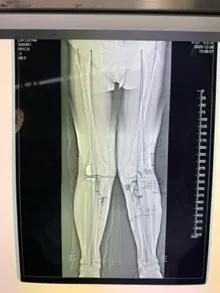

經(jīng)過詳細(xì)的體格檢查、影像學(xué)評(píng)估和三維重建,醫(yī)療團(tuán)隊(duì)確認(rèn)鮑奶奶的情況非常適合進(jìn)行膝外側(cè)單髁置換術(shù)。這種微創(chuàng)手術(shù)創(chuàng)傷小、恢復(fù)快,能夠最大程度保留膝關(guān)節(jié)的自然結(jié)構(gòu)和功能。

手術(shù)當(dāng)天,骨科團(tuán)隊(duì)采用微創(chuàng)切口,僅約8厘米,遠(yuǎn)小于傳統(tǒng)全膝關(guān)節(jié)置換手術(shù)切口。術(shù)中精準(zhǔn)定位,僅置換病變的膝關(guān)節(jié)外側(cè)間室。

手術(shù)使用了最新的單髁假體系統(tǒng),這種假體設(shè)計(jì)更符合人體工程學(xué),能夠更好地恢復(fù)膝關(guān)節(jié)的自然運(yùn)動(dòng)軌跡。

整個(gè)手術(shù)過程僅持續(xù)約1小時(shí),術(shù)中出血不到100毫升。術(shù)后鮑奶奶被送回病房,生命體征平穩(wěn)。